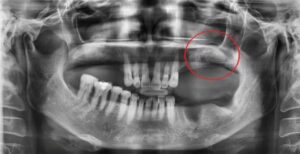

상악동 거상술 환자 실제 사례

부비동은 윗턱 위에 위치한 빈 공간으로, 일부 치아 뿌리가 여기까지 닿습니다. 치아를 발치한 후 남은 뼈가 얇아지면 임플란트를 안정적으로 심기 어려울 수 있습니다.

상악동 거상술로 인해 뼈를 식립하고 뼈의 두께가 (흰색 부분) 한층 두꺼워진 것을 확인할 수 있습니다. 이 후 충분한 검사 후 임플란트를 진행했습니다.